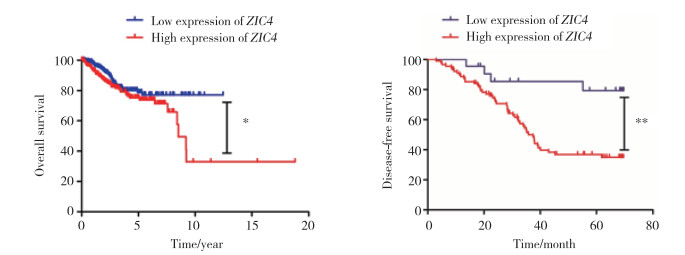

2.3 ZIC4基因表达的生存分析

对应用TCGA数据库获取的子宫内膜癌患者信息进行单因素Keplan-Meier分析,结果显示,ZIC4高表达与总体生存期缩短明显相关(P < 0.05),见图 2。

|

| 图 2 ZIC4表达与子宫内膜癌患者生存期及无病生存率的单因素Keplan-Meier分析 Fig.2 Kaplan-Meier survival curves of cases with high and low ZIC4 expression levels in patients with endometrial cancer |

ZIC基因最早于1994年由ARUGA等[11]在筛选成年鼠小脑cDNA文库时发现,因在小脑颗粒细胞里大量编码锌指蛋白表达而命名为ZIC基因,1995年ZIC基因被克隆[12]。此后,ZIC基因家族的其他成员ZIC2~5逐渐被人们发现[13]。全部5个ZIC基因都具有三外显子结构,其中锌指结构域编码位于每个基因的C-末端。锌指蛋白结构域可以结合DNA序列,也可被Gli锌指蛋白结合,Gli蛋白和ZIC锌指结构域中也存在类似的特异性结合序列[14-15]。ZIC报告基因的激活在一定程度上依赖于Gli靶序列的存在[16]。Gli蛋白在SHH(Sonic hedgehog)信号转导通路中扮演至关重要的角色,在细胞的分化、增殖、迁移侵袭以及凋亡等生理过程中起着举足轻重的作用[17]。ZIC1和ZIC4在人染色体3号(小鼠染色体9)紧密连接。ZIC4在转录调控中通常与ZIC1一起工作[18]。PALUSZCZAK等[19]发现头颈癌细胞中ZIC1和ZIC4基因的启动子被甲基化,Wnt信号通路被激活,其中ZIC4甲基化与口腔癌患者淋巴结转移相关,ZIC4的甲基化被认为可能是新的头颈鳞状细胞癌预后指标。已有研究结果表明,血浆DNA的ZIC1启动子甲基化速率对于GC的早期筛选和肿瘤发生的监测具有重要意义。ZIC1启动子甲基化速率和CEA水平(并行测试)的组合检测可以提高胃癌的早期诊断率[20],也有研究[21]认为ZIC1启动子的甲基化可能作为肝癌的潜在生物学指标。此外,在甲状腺癌、结肠癌等肿瘤中均可检测到ZIC1基因表达异常,以及启动子发生甲基化[22-23]。以上研究说明DNA甲基化可能是ZIC基因调控的重要机制之一。已有文献[24]报道ZIC1基因在子宫内膜癌组织中过表达,但在正常组织中低表达,ZIC1的表达下调有助于抑制细胞增殖,抑制肿瘤生长。关于ZIC4与子宫内膜癌的相关研究暂无报道。本研究通过免疫组化法检测了ZIC4在不同子宫内膜石蜡组织中的表达,结果表明ZIC4在子宫内膜癌组织中呈高表达。本研究还分析了ZIC4表达与临床病理资料间的关系,结果发现,ZIC4的表达高低与临床分期、组织分化、肿瘤浸润深度及淋巴结转移等临床病理参数密切相关。同时,本研究分析了ZIC4与子宫内膜癌预后的相关性,结果提示子宫内膜癌中ZIC4高表达可导致预后生存率较差。